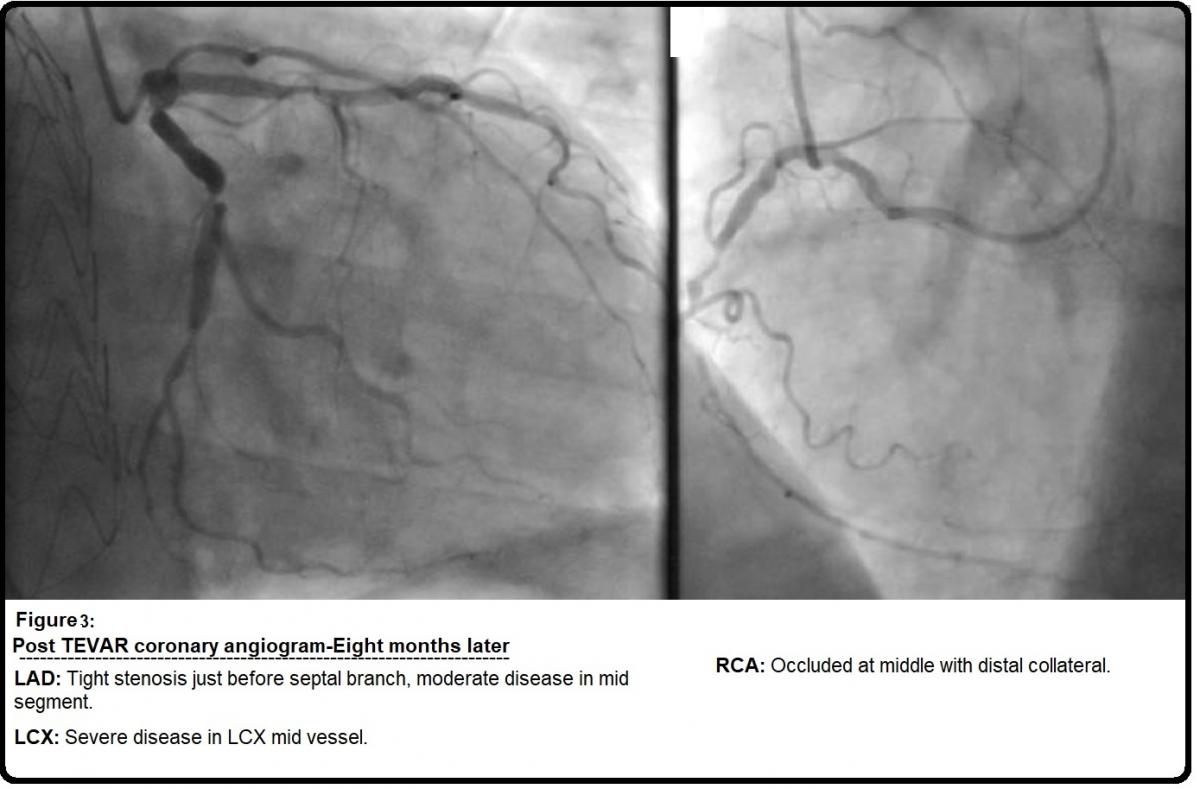

The patient in this video was a 69-year-old man who presented to the emergency department with sudden onset of chest and back pain. He was a smoker, otherwise there was no significant comorbidity, however, on admission he was markedly hypertensive. CT aorta revealed an acute type B dissection with an entry tear at the origin of the left subclavian artery; left kidney was malperfused and true lumen was significantly compressed by the false lumen (Figure 1). He developed acidosis that was a sign of organs ischaemia. He underwent emergency procedures that included left carotid-subclavian arteries bypass graft with 6 mm Dacron graft and percutaneous thoracic endovascular arterial repair in Ishimaru's zone 2, 3, 4 (TEVAR-Stent; Conformable GORE® Thoracic Endoprosthesis) (Figure 2). He was discharged on the sixth postoperative day in good condition. Subsequent CT scan showed the diameter of the ascending aorta 53 mm, while coronary angiogram revealed LAD stenosis (tight stenosis just before septal branch, moderate disease in mid segment), LCX stenosis (severe disease in LCX mid vessel), and RCA stenosis (Occluded at middle with distal collateral) (Figure 3). Transthoracic echocardiogram showed trivial aortic regurgitation, 39 mm sinus diameter and normal LV & RV systolic function.

Taking consideration of his recent type B dissection, aortic dimensions, and three vessels coronary disease, he was offered surgery that he accepted. Lupiae technique for aortic arch debranching was chosen as percutaneous thoracic endovascular arterial repair involved Ishimaru's zone 2. Eight months later of TEVAR-Stent, he underwent resuspension of aortic valve with remodelling of the aortic root, debranching of aortic arch, replacement of proximal ascending aorta (Lupiae technique), and concomitant triple coronary artery bypass graft (SVG-LAD, SVG-OM1, and SVG-RCA). Operative findings: The ascending aorta was frankly dilated up to the origin of the innominate artery; the arch portion close to the innominate artery was calcified, while the aortic root mainly effaced at the noncoronary sinus. Cumulative bypass time was 230 minutes; cumulative cross clamp time was 146 minutes. He was admitted one day before the operation and was discharged on the seventh postoperative day with very good recovery.